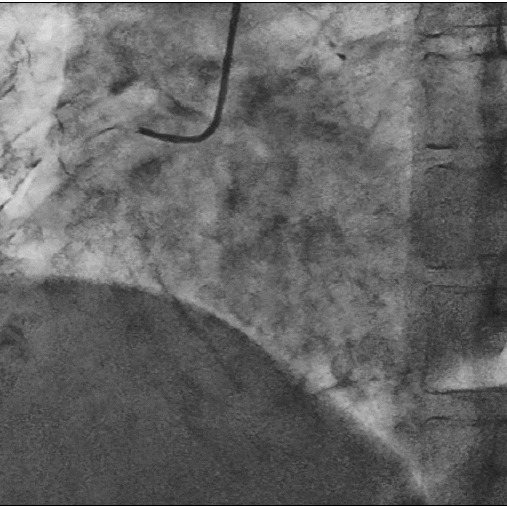

造影图:

LM呈鸟嘴样狭窄,

LAD为迂曲弥漫性病变,中段最重处狭窄80%,曾搭桥已闭塞。RCA曾植入支架,中段支架内反复再狭窄。